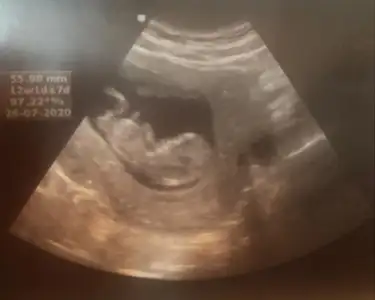

Tahmininiz nedir ?😊

Eklentiler

• 20200122_190950.webp

20200122_190950.webp

74,9 KB · Görüntüleme: 73

• 20200122_191032.webp

20200122_191032.webp

67,7 KB · Görüntüleme: 67